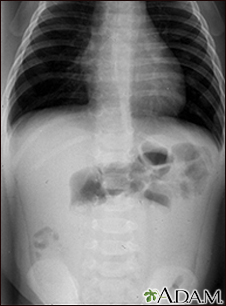

Intussusception - x-ray